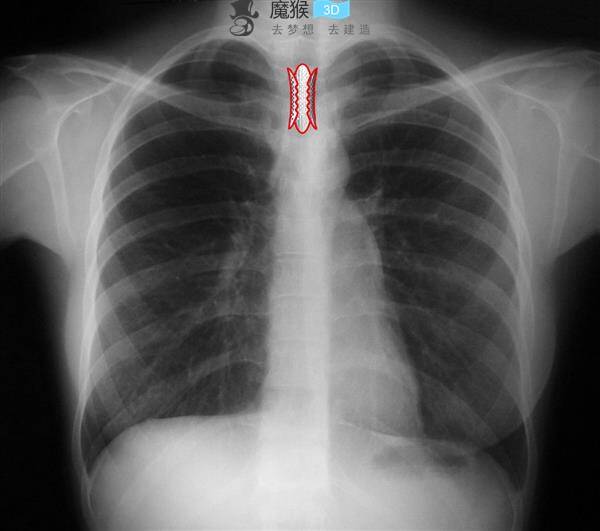

Stephen Lawrence獲獎(jiǎng)的建筑師Anna Liu和總部位于倫敦的Tonkin Liu的Mike Tonkin開(kāi)發(fā)了一種名為Shell Lace Stent的創(chuàng)新醫(yī)療設(shè)備,用于患者的氣管。原型支架基于該公司的標(biāo)志性Shell Lace Structure,這是一種“通過(guò)十年的建筑和工程應(yīng)用研究設(shè)計(jì)和開(kāi)發(fā)的單面結(jié)構(gòu)技術(shù)”,并使用數(shù)字設(shè)計(jì)軟件和3D打印進(jìn)行原型設(shè)計(jì)。

魔猴網(wǎng)了解到,Tonkin Liu率先采用了基于單面貝殼花邊設(shè)計(jì)的結(jié)構(gòu) - 例如去年完成的赫爾太陽(yáng)門雕塑,以及超輕質(zhì)的涼亭,橋梁和塔樓。新的支架設(shè)計(jì)發(fā)揮自然向外的壓力,減少運(yùn)動(dòng)的風(fēng)險(xiǎn) - 這是影響目前使用的產(chǎn)品的問(wèn)題之一。為了適合醫(yī)療用途,3D打印原型比之前為其建筑應(yīng)用創(chuàng)建的原型小500倍,并與Arup和自然歷史博物館合作開(kāi)發(fā)。

氣管支架通常用于支持氣管移植,并在喉癌,創(chuàng)傷和老年的情況下治療塌陷的氣道。支架通常被制造為非定制的管狀網(wǎng)。 Tonkin Liu的支架設(shè)計(jì)是C形而不是管狀,目的是更好地適應(yīng)每個(gè)患者喉嚨的個(gè)體形狀。 C形設(shè)計(jì)一旦插入就會(huì)展開(kāi),從馬蹄蓮花瓣的幾何原理中汲取靈感。該裝置由醫(yī)用級(jí)硅制成,具有穿孔表面,允許透氣性和藥物遞送至氣管組織。

Shell Lace Stent現(xiàn)已被批準(zhǔn)為正在申請(qǐng)專利。 Tonkin Liu正在與研究合作伙伴合作,將創(chuàng)新推向市場(chǎng),并探索該技術(shù)在人體其他部分的更廣泛應(yīng)用。原型支架的開(kāi)發(fā)得到了2016年政府資助的英國(guó)Innovate計(jì)劃的資助。